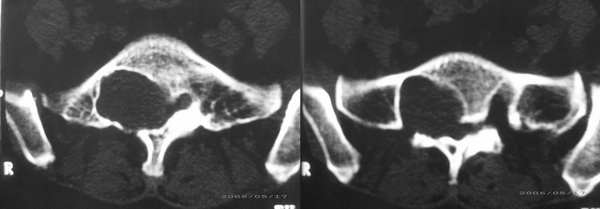

患者,女性,60岁。腰痛、腿痛一周余,临床医生考虑:椎间盘突出,行ct及mr检查

病灶为长t1长t2信号,对s1椎体是压迫吸收,应首先考虑骶管囊肿。建议增强扫描。

征象:1、骶椎管偏右侧囊性病变,长t1长t2改变,均匀。2、慢性病变过程,邻近骨质有吸收变薄。

考虑:盲囊蛛网膜囊肿。

S1椎长T1长T2信号,与蛛网膜下腔相连,边界清晰,CT可见局部骨质吸收,边缘硬化改变。支持骶管囊肿。